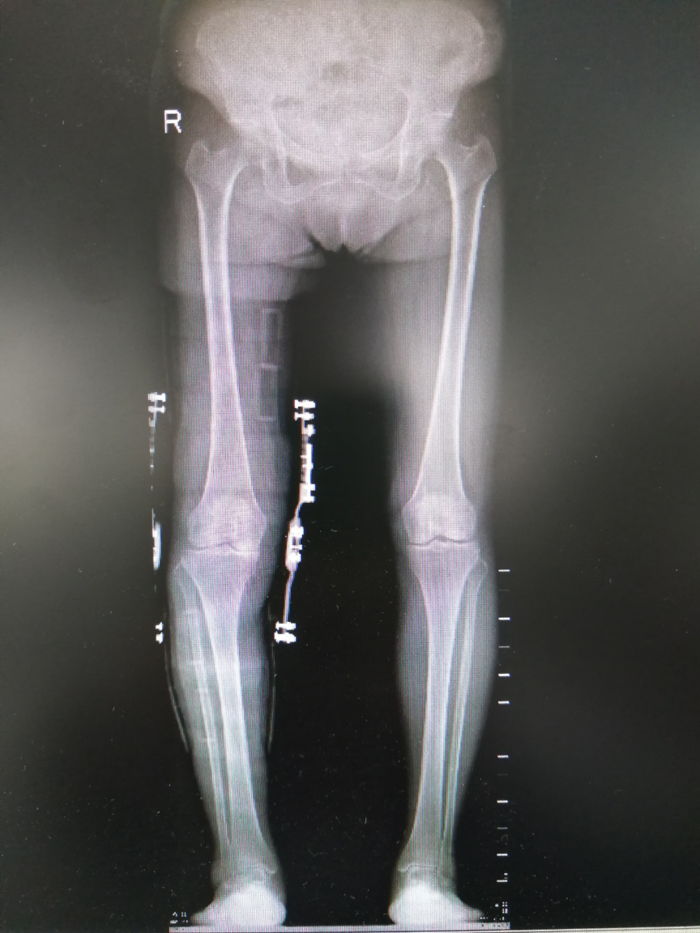

患者适配精准调整后佩戴矫形器拍摄X光片,做到精准矫正与治疗。患者穿戴矫形器后再行影像学检查,结果:骨盆及下肢对称,膝关节边缘骨质增生,关节间隙未见明显异常。

下图为患者穿戴矫形器的双下肢力线全长X光片